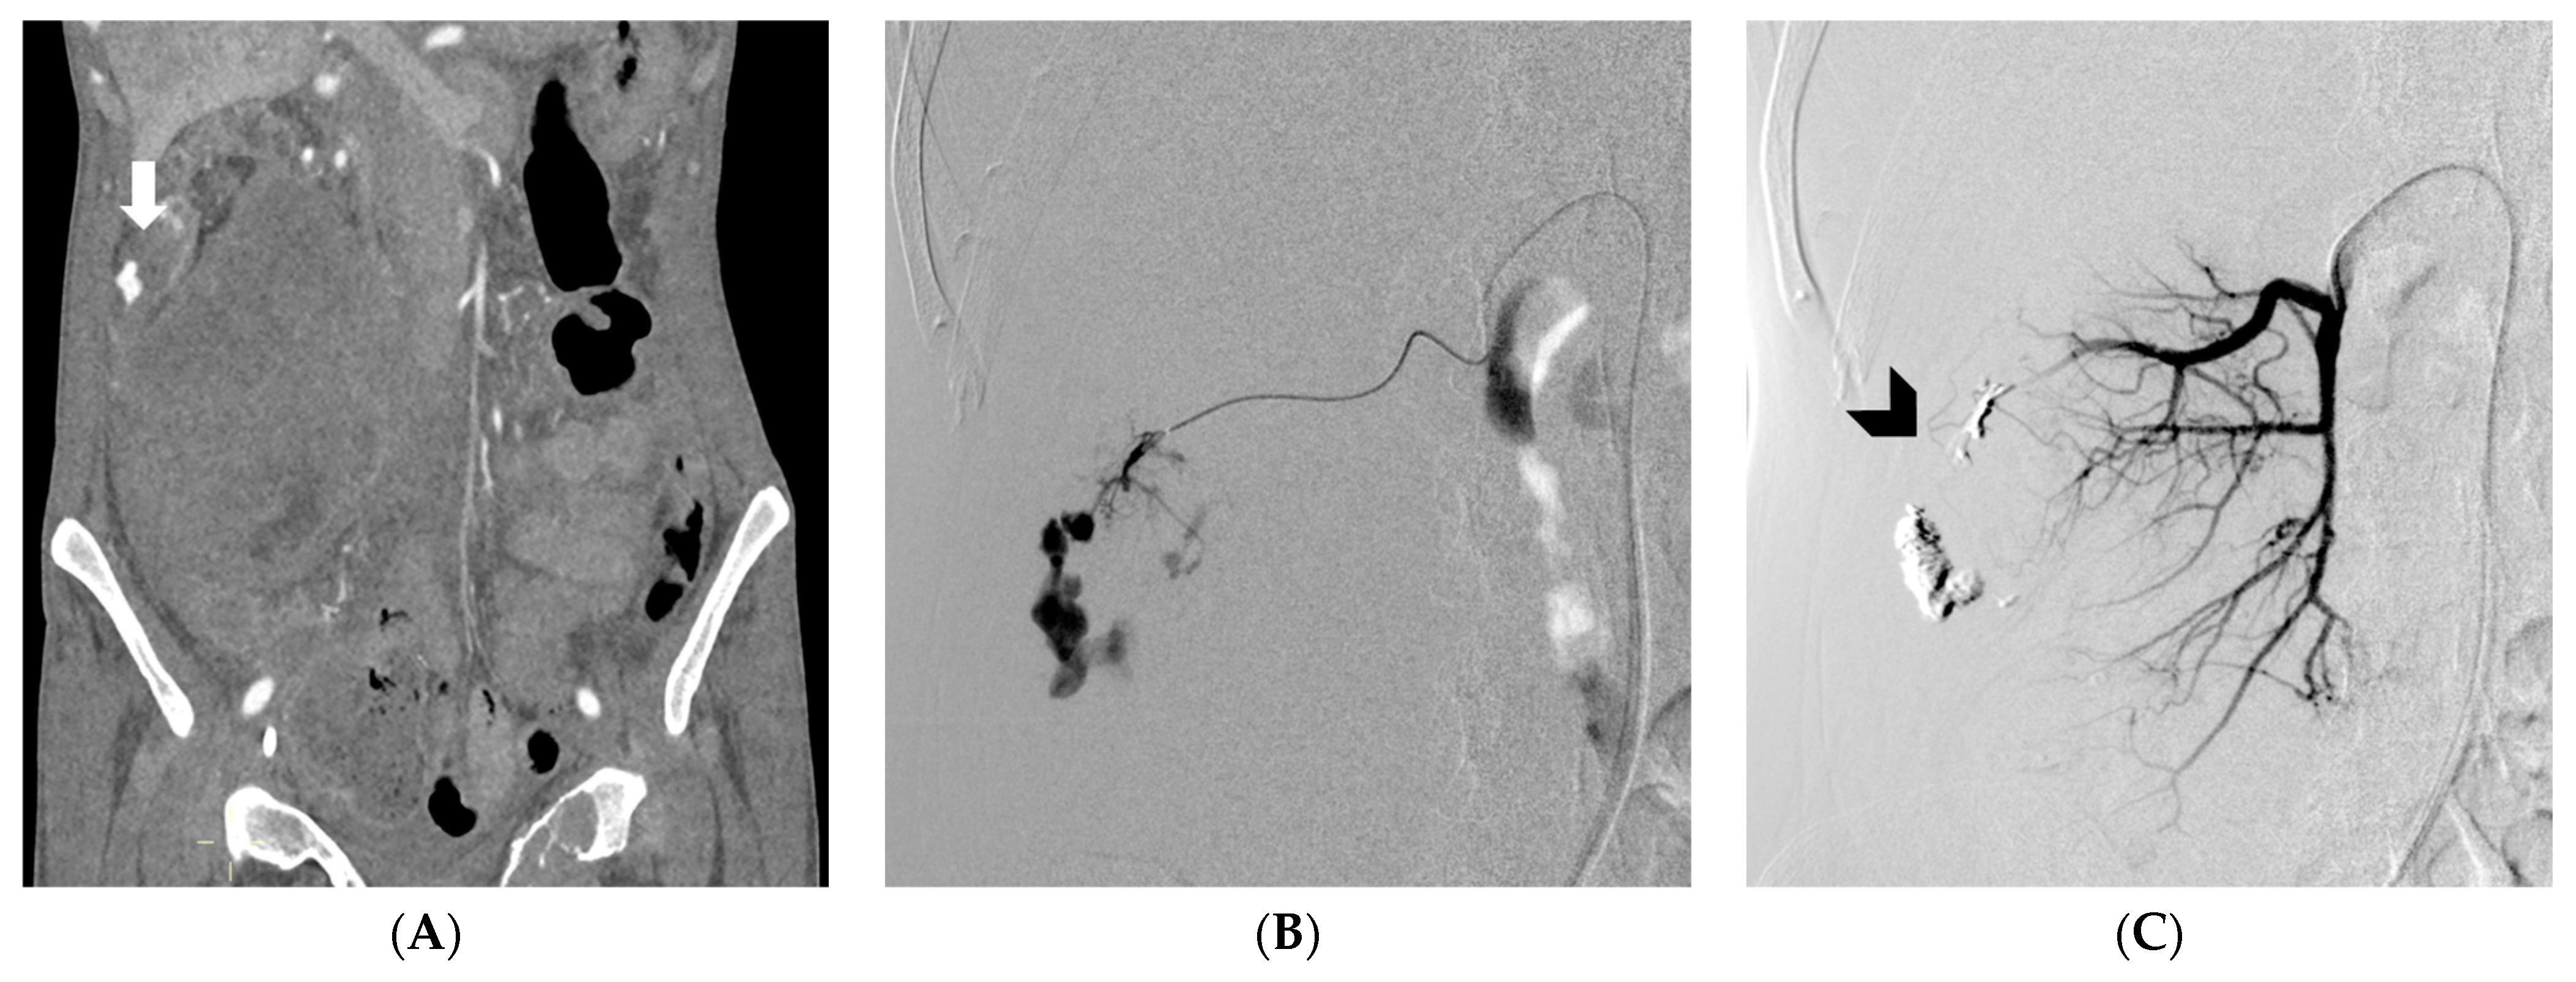

- Atzori, G.; Diaz, R.; Gipponi, M.; Cornacchia, C.; Murelli, F.; Depaoli, F.; Sparavigna, M.; Barbero, V.; Petrocelli, F.; Pitto, F.; et al. A Case of Life-Threatening Bleeding Due to a Locally Advanced Breast Carcinoma Successfully Treated with Transcatheter Arterial Embolization. Curr. Oncol. 2023, 30, 2187–2193. [Google Scholar] [CrossRef]